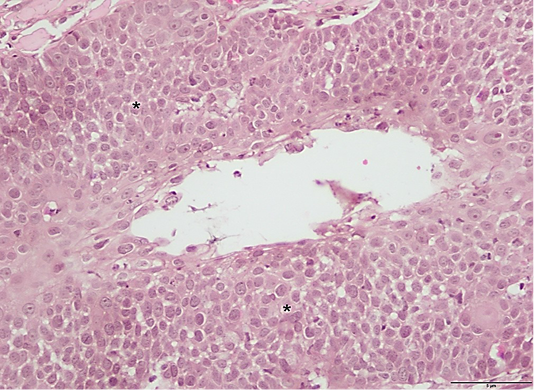

Figure 3

Histologic section of the excised tissue showing epidermal dysplasia (*). (H&E stain, 40x). Scale; 5µm.